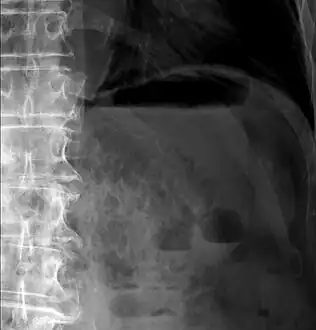

- Upright AP radiograph showing gas in the wall of the small bowel in the left upper quadrant indicative of pneumatosis intestinalis.